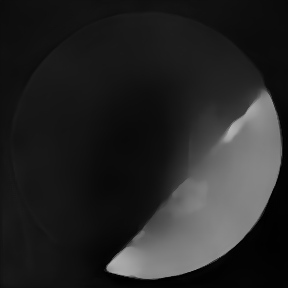

Figure 12: Two examples of photoacoustic images, ground truth images (a)(e) and comparisons of the reconstructions with Alg1 (b)(f), Alg2 (c)(g) and Alg3 (d)(h). None of the measures was able to assess the relevant quality properties for both examples correctly.

As examples for PA image reconstructions, we show in Figure 12 reconstructed images containing estimated distributions of the optical absorption coefficient from cross-sectional photoacoustic images of piecewise-constant test objects (phantoms), cf. (citep \@BBN(Grohl et al., 2023)). These images were the result of a two-stage process to solve the PA inverse problems. PA data was acquired with a commercial photoacoustic imaging system (MSOT InVision 256-TF, iThera Medical GmbH, Munich, Germany) and processed with three different algorithms (referred to as Alg1, Alg2, Alg3). For the visualization and assessment, the outputs of the algorithms were clipped with the reference image’s maximum.

Alg1 corrects a reconstructed PA image by using the light fluence obtained from simulations based on the reference measurements. Alg2 and Alg3 are deep-learning algorithms that are trained to directly estimate the absorption coefficient from the reconstructed image. Alg2 was trained with simulated data and Alg3 was trained with experimental data. The reference absorption coefficients are obtained by using a double-integrating sphere (citep \@BBN(Pickering et al., 1993)) setup as a complementary measurement system, which only yields point estimates for homogeneous material samples. Because of the piecewise-constant nature of the used phantoms, one can fabricate an additional batch of the material used for the test object, measure it, and relate the calculated properties to the test object. For any complicated objects or in vivo images, this process would be unfeasible.

FR-IQA mismatches

Photoacoustic images are typically sparse, which complicates the application of image-based quality measures. In the original paper (citep \@BBN(Grohl et al., 2023)), the qualitative assessment was conducted manually. In that assessment, Alg3 should perform best, Alg1 second best, and Alg2 worst across the test images. As this kind of manual assessment is not feasible for larger data sets, and may naturally also introduce inconsistencies as well as biases, automation is needed. However, when PSNR and SSIM are applied to the images these intended results cannot be reproduced. SSIM wrongly assesses that Alg1 performs worst throughout all both images (Figure 12), LPIPS for the second example. PSNR wrongly judges Alg1 as the best rather than Alg3 and does not give much lower results for Alg2 than Alg3, despite the introduction of artefacts that lead to significant degradation of image quality.

Depending on the goal of the data analysis, desired quality properties may differ here. Artifacts might introduce structures into the image that could be mistaken for regions of interest. On the other hand, an inaccurate estimation of the absolute absorption coefficient might lead to errors in the estimation of functional tissue parameters, such as blood oxygenation, that are important to assess the health status of a patient. Therefore, targeted IQA measures that are indicative of success given a desired use case are required for the objective assessment of algorithms for quantitative PAI and would allow fast advances in the still evolving field.